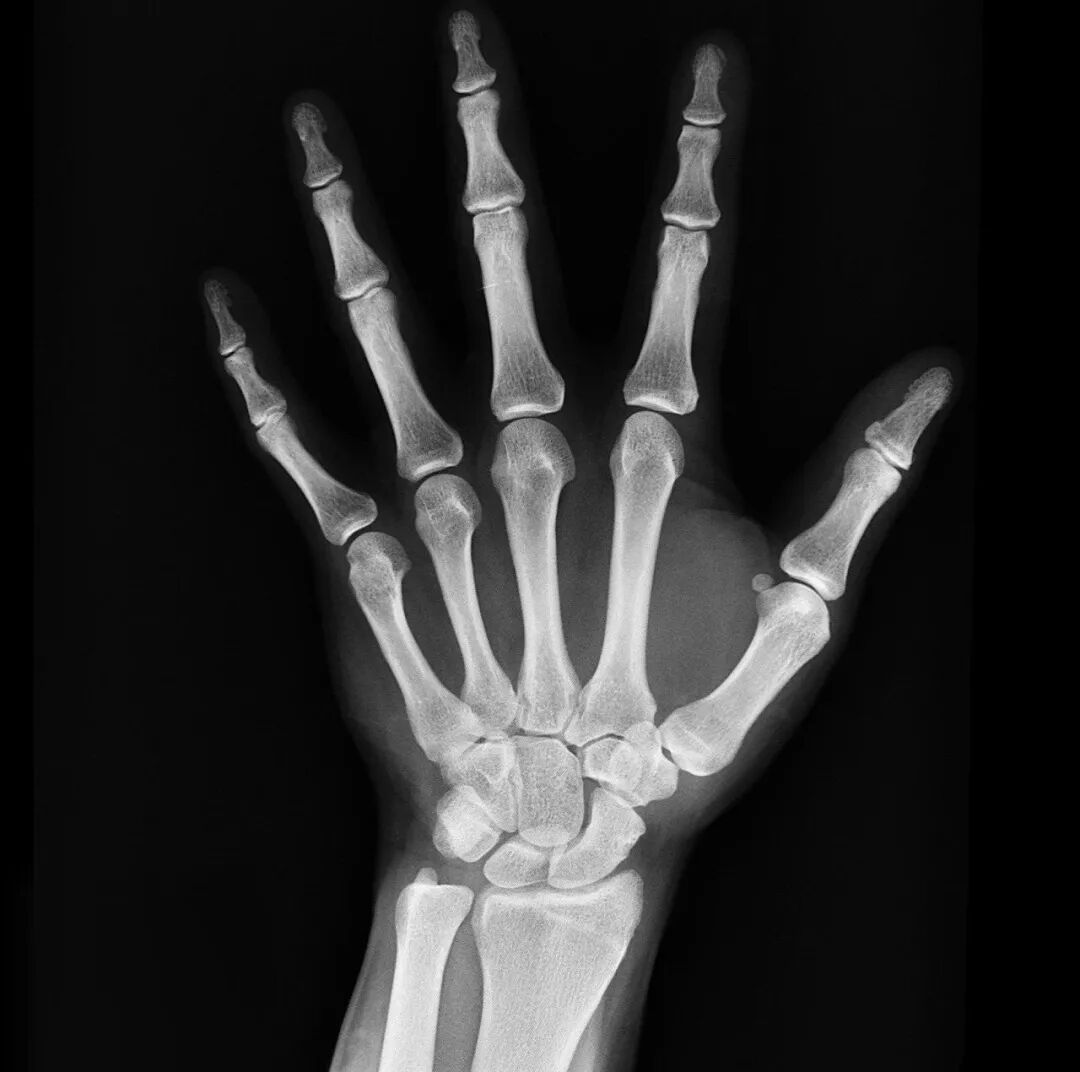

最常用X光片

诊断不明确,可用CT

骨骼、四肢